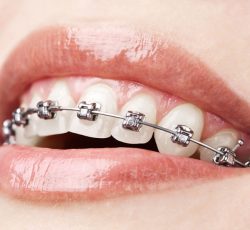

Aparelho Ortodôntico Fixo Convencional:

Transforme seu sorriso usando brackets e fios metálicos, corrigindo diversos problemas dentários, permitindo controle preciso e resultados visíveis. Agende uma consulta e conquiste um sorriso mais confiante e saudável.